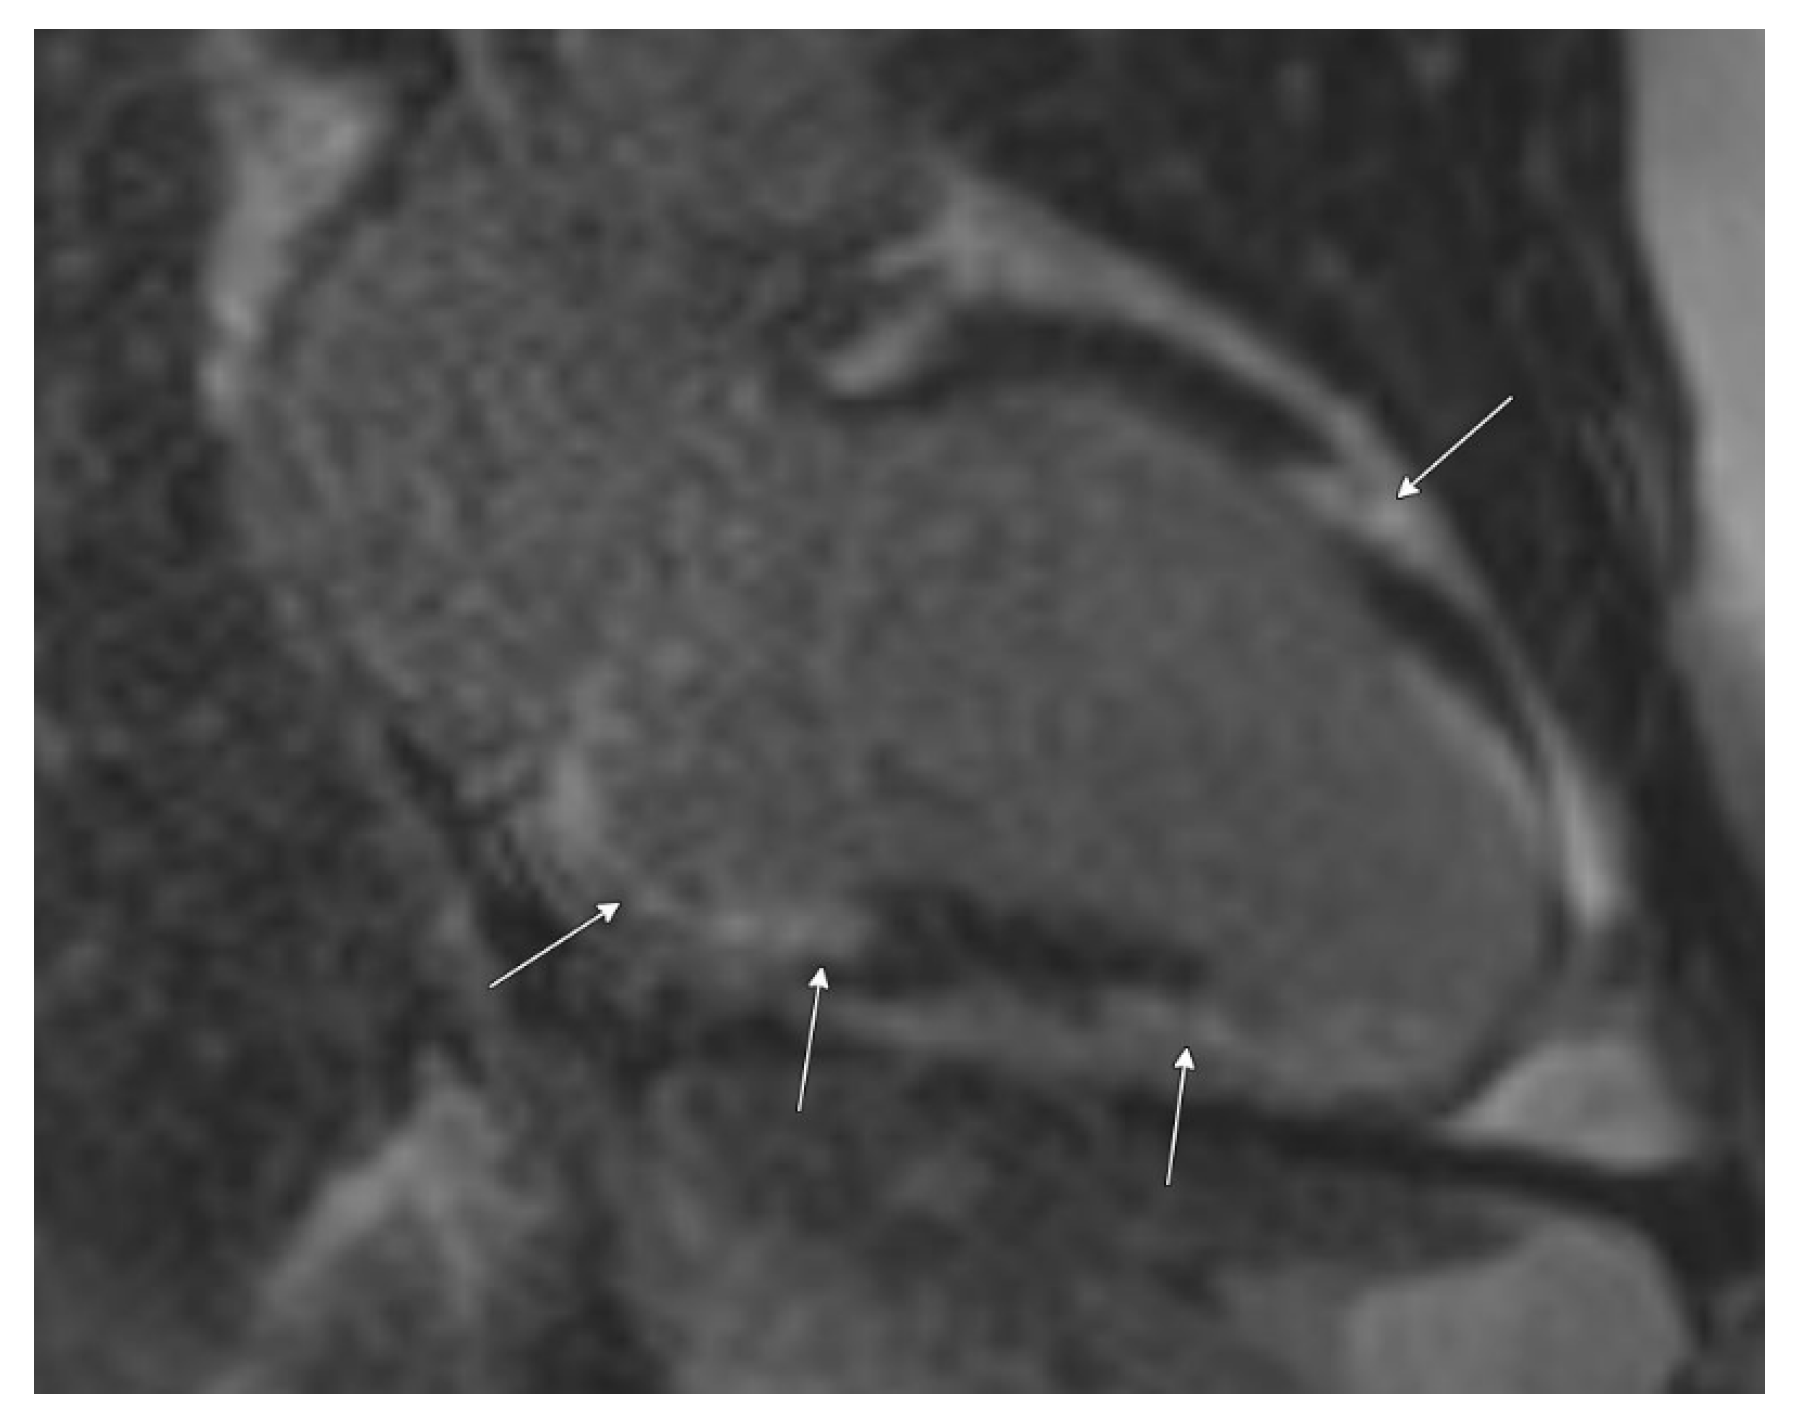

Cardiac MRI confirmed biventricular dysfunction, with left ventricular ejection fraction of 12%, right ventricular ejection fraction of 18%, basal septal akinesis/dyskinesis, and extensive abnormal late gadolinium enhancement, further supporting the suspicion of CS (Figure 3 and Figure 4). While there were no clinical signs of non-sarcoid inflammatory cardiomyopathy, a Positron Emission Tomography (PET) scan showed a very large area of diffuse myocardial FDG uptake with associated perfusion abnormalities, as described in the bull’s eye diagram, further supporting the diagnosis of CS (Figure 5). Except for cardiac abnormalities, a full-body CT PET was negative. CT coronary angiography revealed patent coronary arteries, while CT pulmonary angiography showed chronic nonocclusive segmental acute pulmonary embolus in the posterior right lower lobe without right heart strain. Ultrasonography Doppler of the lower extremities identified subacute nonocclusive superficial venous thrombosis involving the small saphenous vein, consistent with the patient’s history of KT syndrome.

Figure 4.

Cardiac MRI with late post-gadolinium-enhanced inversion recovery imaging in a short axis view at the base demonstrates extensive abnormal left ventricular myocardial late enhancement in a mid-wall and epicardial predominant distribution, particularly involving the basal inferior wall, septum (yellow arrow), and inferolateral wall (white arrow).